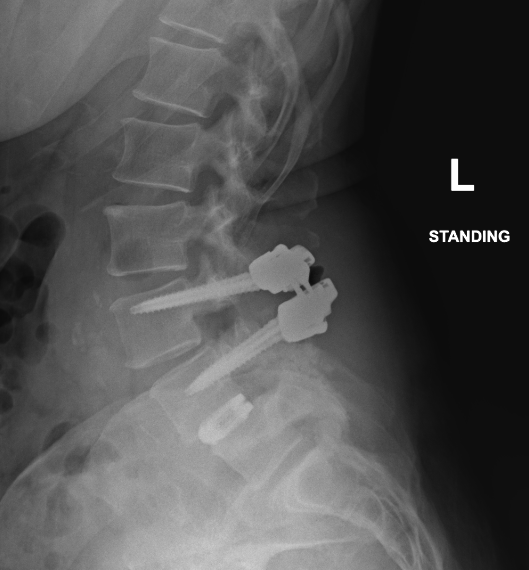

We are proud to announce that Dr. Brenton Pennicooke recently performed the very first TOPS (Total Posterior Spine) procedure within the BJC system by a WashU Medicine provider. The procedure, performed at Barnes-Jewish St. Peters Hospital, offers a motion-preserving alternative to traditional spinal fusion. This milestone represents an important step in expanding advanced spine care at WashU Medicine.

The TOPS implant works by stabilizing the spine after relieving pressure on the nerves while still allowing natural movement. Preserving motion at the treated level helps maintain normal spine mechanics and may reduce stress on adjacent segments, a common concern with fusion.